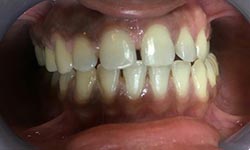

(9) Metal Ceramic Crowns

Before Treatment

After Treatment

Mr. Shiv Narayan Singh,aged 78yrs, came with a concern of multiple broken and mobile teeth with difficulty in chewing food. So, multiple RCTs followed by metal-ceramic crowns were delivered to the patient ,restoring his beautiful smile.